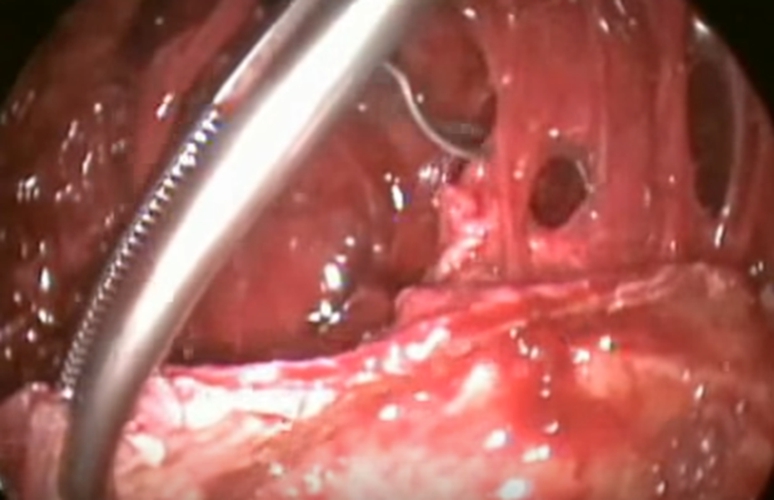

結核性胸膜炎胸腔鏡

結核性胸膜炎引流

結核性胸膜炎胸腔鏡的